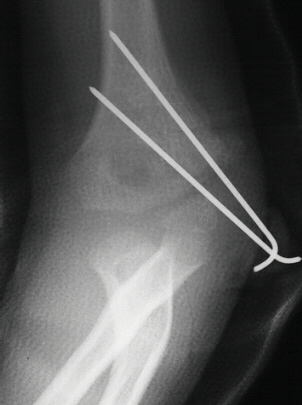

A five year and six month old white male sustained a fall

onto his outstretched right arm with immediate complaints of pain

and swelling in his right elbow. The child was unable to move

his arm secondary to pain. He was on the play ground and the fall

was not witnessed. Physical examination revealed swelling, tenderness

and crepitus over the lateral aspect of the elbow. The skin was

intact and neurovascular examination of the right upper extremity

was without deficits. The patient was taken to the operating room

where under general anesthesia and tourniquet control, the fracture

was exposed utilizing an anterolateral approach. Two diverging

k-wires were placed across the fracture site.